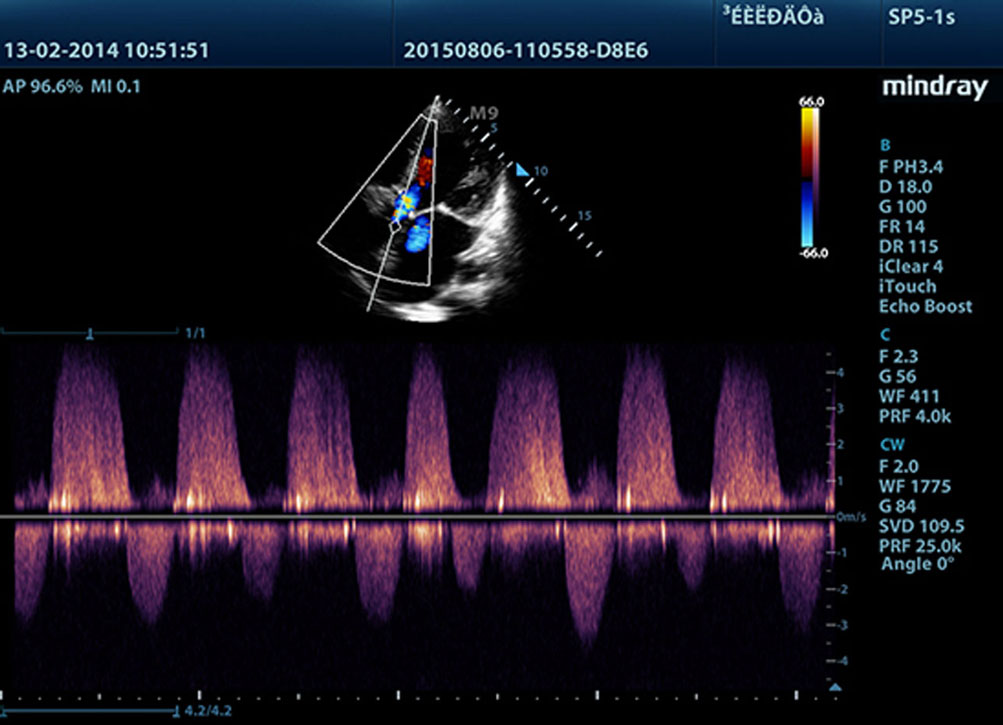

• Free Xros CM™

Огибающий (нелинейный) анатомический М-режим. Позволяет получить полную информацию о движении сердечной мышцы в различных фазах сокращения и одновременно определять степень синхронизации миокарда. Точность результатов обеспечивается высокой частотой кадров.

• Auto EF

Интеллектуальный способ анализа изображений двухмерной эхокардиографии для автоматического распознавания диастолических и систолических кадров и вывода результатов КДО, КСО, реакции выброса и т. д. методом Симпсона.

• TDI

С помощью тканевой доплеровской визуализации можно определять количественные показатели движения и функционирования сердечной мышцы, используя режимы полной визуализации для быстрой и непосредственной диагностики.